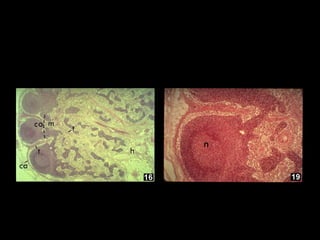

SLEZINASLEZINA

Raspored pojedinih subpopulacija limfocita iRaspored pojedinih subpopulacija limfocita i

akcesornih ćelija u slezini je sličan kao i u limfnomakcesornih ćelija u slezini je sličan kao i u limfnom

čvoru.čvoru.

Periarterijski limfni omotači su sastavljeni odPeriarterijski limfni omotači su sastavljeni od

pomažućih T-limfocita (2/3) dok 1/3 sačinjavajupomažućih T-limfocita (2/3) dok 1/3 sačinjavaju

citotoksični T limfociti.citotoksični T limfociti.

Folikule i i germinativne centre čine B-limfociti.Folikule i i germinativne centre čine B-limfociti.

Marginalna zona sadrži B-limfocite, makrofage i TMarginalna zona sadrži B-limfocite, makrofage i T

pomažućepomažuće ćelije.ćelije.

CRVENA PULPA:CRVENA PULPA:

1.BILROTOVE TRAKE:TRAKE:

MAKROFAGIMAKROFAGI

SVE ĆELIJE KRVI (Er,Ly,SVE ĆELIJE KRVI (Er,Ly,

Mo)Mo)

2. SINUSOIDNI2. SINUSOIDNI

KAPILARIKAPILARI

SPECIJALNI VENSKI SASPECIJALNI VENSKI SA

UZDUŽNIM OTVORIMAUZDUŽNIM OTVORIMA